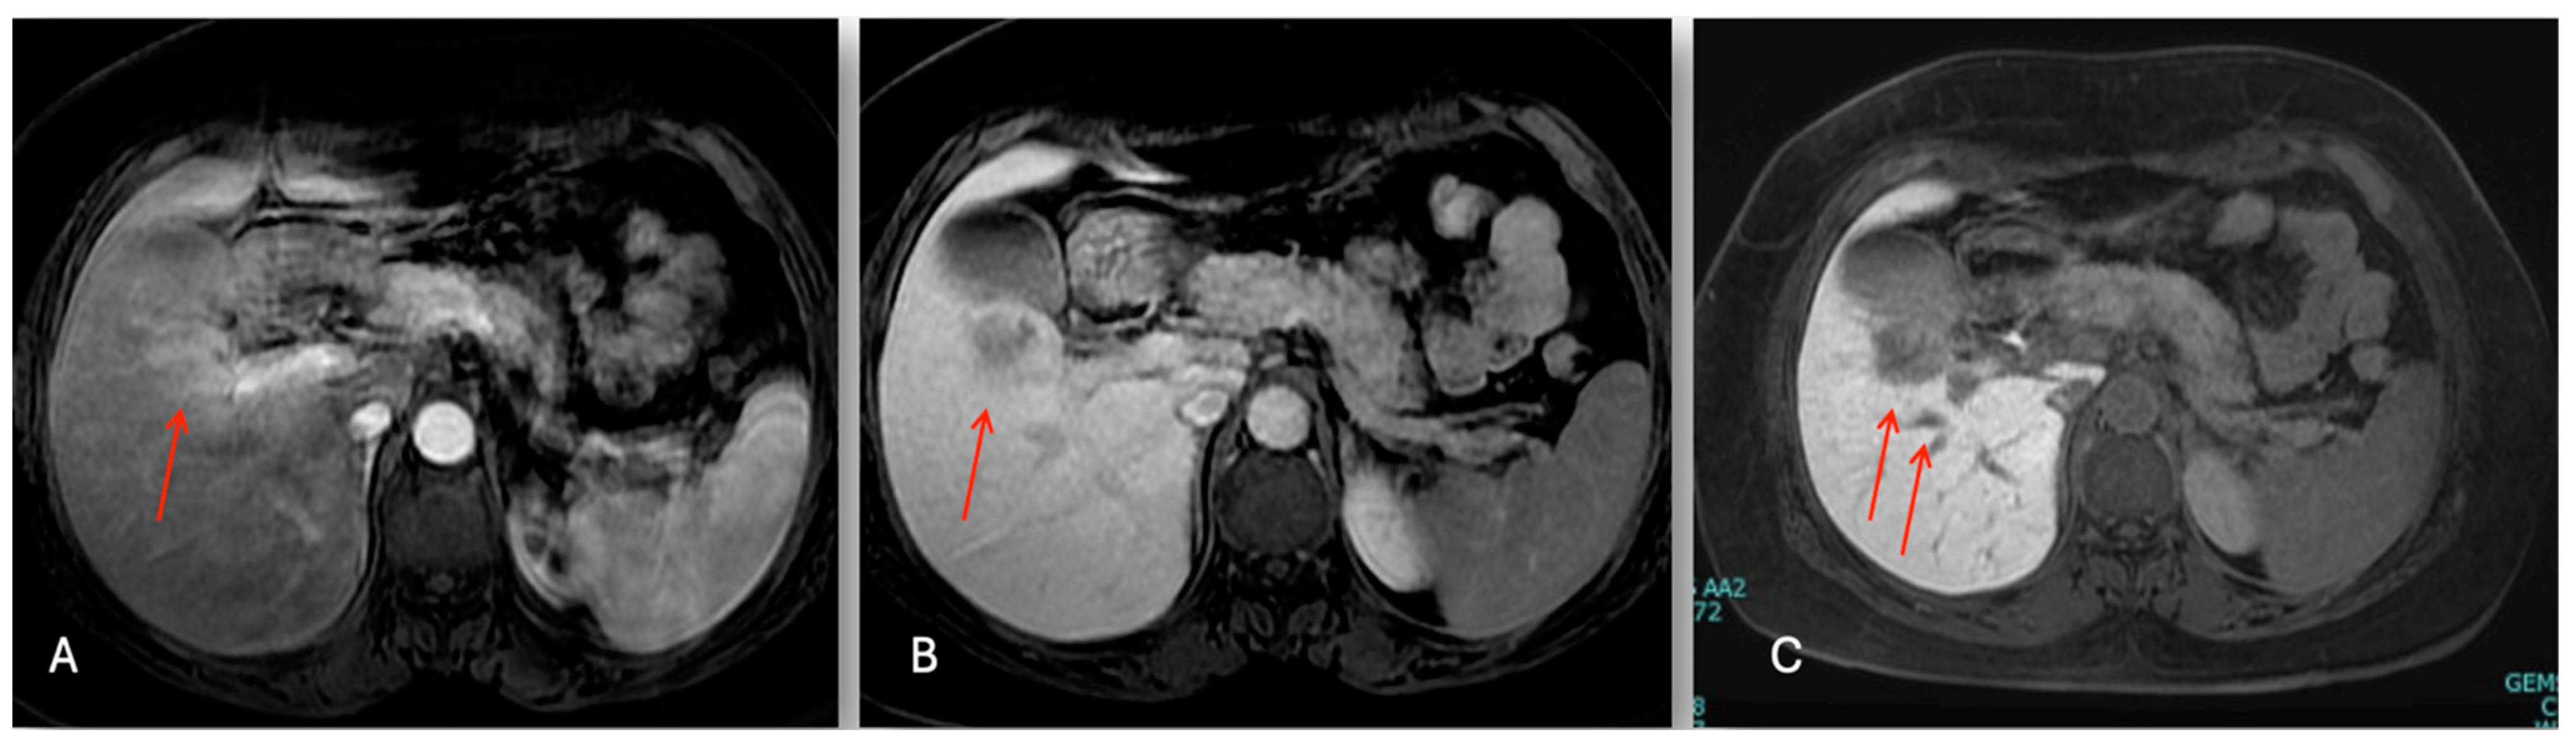

3.2.2. Case 2